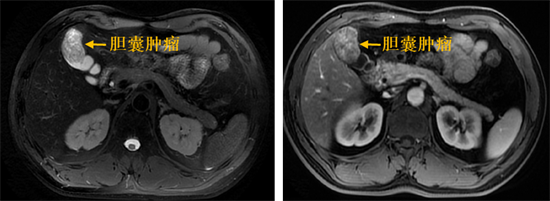

增强磁共振检查提示:胆囊腔内肿块大小40*29mm,动脉期强化明显。肝胆胰外科、微创外科立即组织了全科讨论,科室主任张成武主任医师仔细查看检查结果后认为:胆囊恶性肿瘤可能性大,值得庆幸的是,胆囊与肝脏之间分界尚清晰,暂无肝脏浸润转移,也没有发现局部及远处淋巴结转移迹象。同时,患者年纪较轻,心肺功能等一般情况良好,可尽快安排手术。